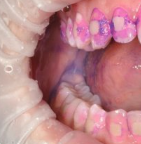

Чистка зубов Air-flow

Профессиональная гигиена особенно важна при ортодонтическом лечении, ведь в повседневной жизни, дома, очень сложно поддерживать должный уровень гигиены полости рта! Даже если вы используете ирригатор и специальные ёршики! В нашей рубрике «до/после» вы видите то, что может быть с зубами при лечении брекетами, если не проводить своевременную чистку у врача-стоматолога. Марухно Дарья Александровна провела профессиональную чистку в несколько этапов, чтобы вернуть пациентке белизну ее собственных зубов! Брекет-система была поставлена не в нашей клинике, и почему пациентка не обратилась за профессиональной помощью раньше-вопрос) Но в данном случае, главное – итог! Кровоточивость после даже обычной чистки в такой клинической ситуации – естественный результат. Ведь обильный зубной налёт и зубной камень вызывают воспаление дёсен в виде гингивита, а порой даже пародонтита.

Доктор: Марухно Дарья Александровна